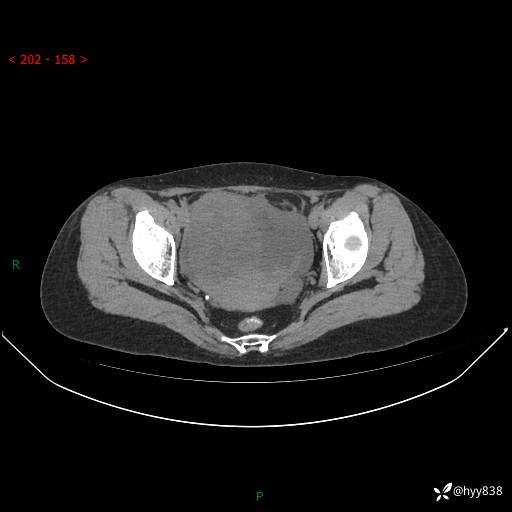

老年女性,尿频2月。超声发现盆腔囊实性占位,CT能否明确诊断---结果公布

现病史:患者绝经3-4年,期间无阴道出血及排液。患者近2月感尿频,自行口服中药治疗,症状无明显缓解。2024-4-25日于我院门诊就诊,行阴道彩超示:子宫肌瘤(大小约12*10mm,后壁),子宫右前方囊实性占位性病变(大小约126*82mm肿块声像,边界尚清,以无回声为主,可见范围约84*27mm稍高回声),内膜3mm。建议手术治疗。门诊以“卵巢囊肿”收入院。 病程中精神、食欲、睡眠可,大小便正常,体重体力无明显变化。

腹盆CT平扫

增强